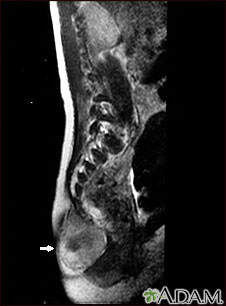

This MRI scan shows a tumor (teratoma) at the base of the spine (seen on the left lower edge of the screen), located in the sacrum and coccyx (sacrococcygeal) area. Teratomas are present at birth and may contain hair, teeth, and other tissues.